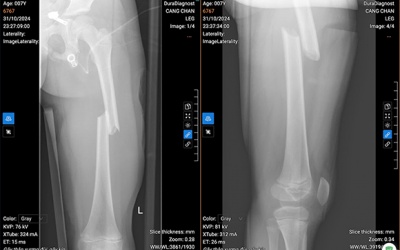

03/11/2024 15:41

Bệnh viện Nhi Hà Nội vừa phẫu thuật thành công cho một bệnh nhi 7 tuổi bị gãy xương đùi, bằng kỹ thuật đóng đinh nội tủy. Đây là phương pháp phẫu thuật ít xâm lấn, xương gãy...